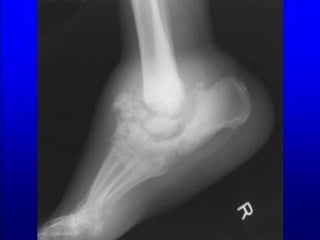

Infection involving structures deeper than

skin and subcutaneous tissues such as

abscess, osteomyelitis,

septic arthritis, fasciitis.

Erythema > 2 cm

No systemic inflammatory response

signs.

GRADE 3 (MODERATE INFECTION)